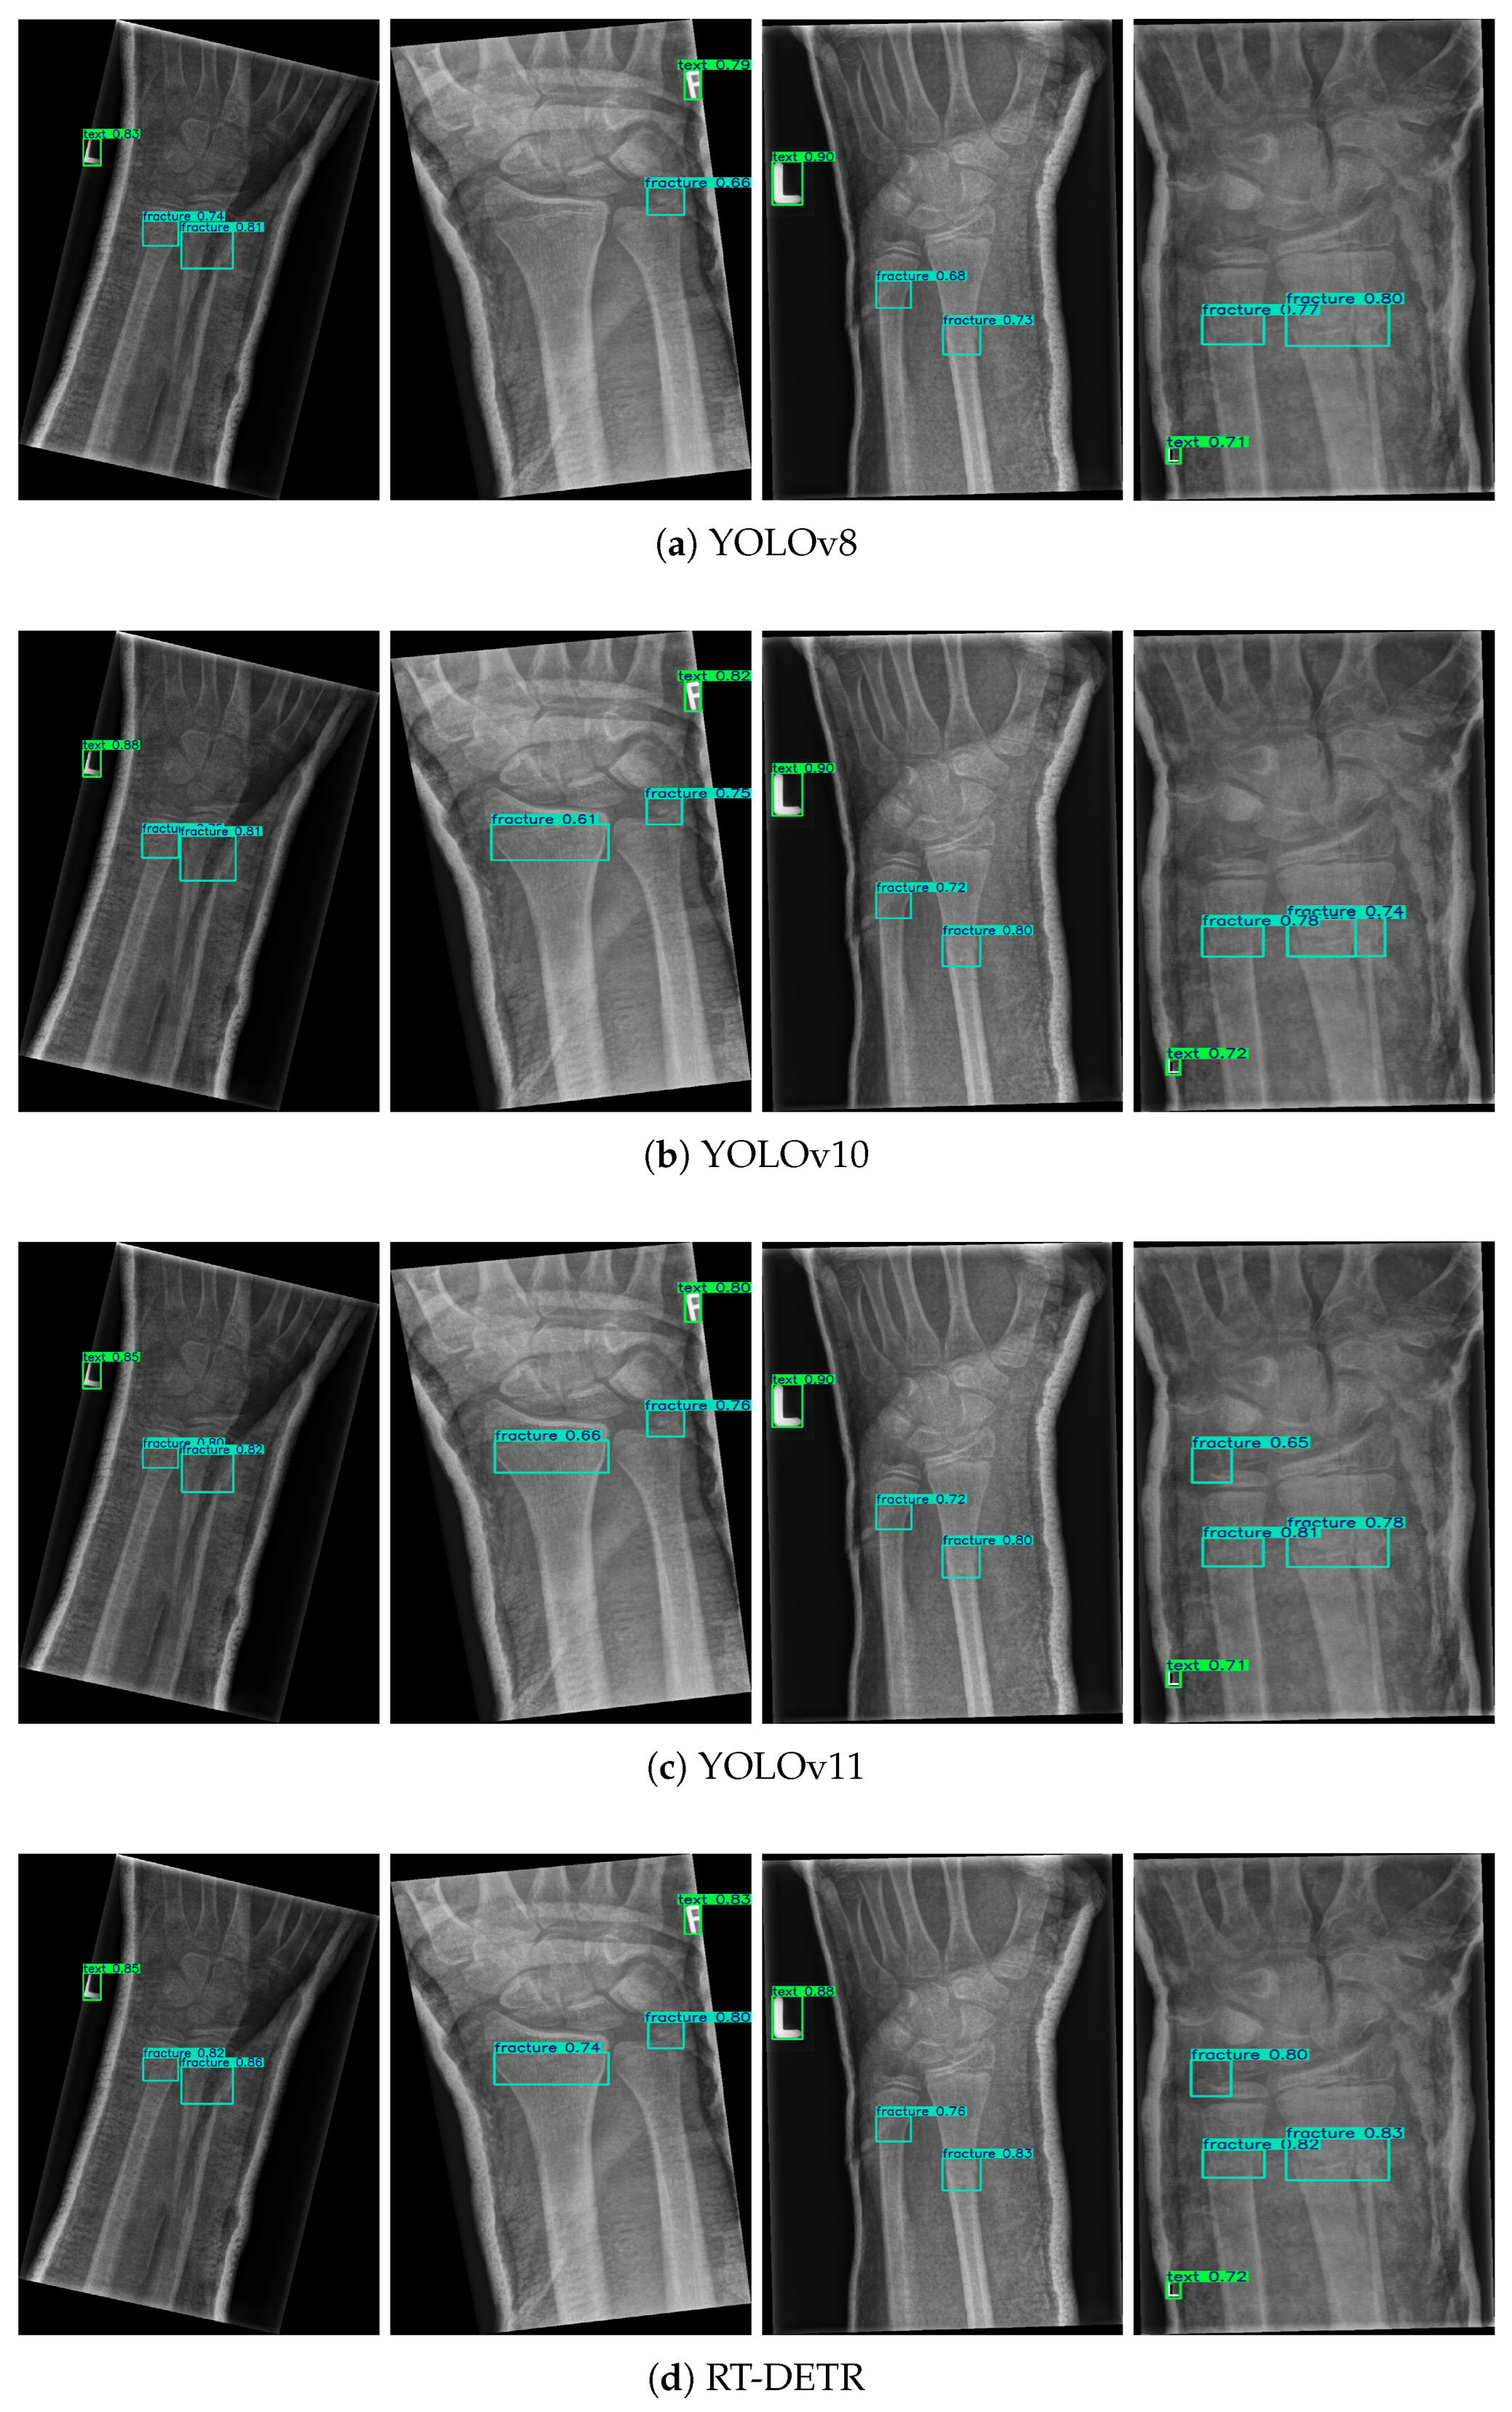

3.1. Main Performance Evaluation

| Models | Parameters | Recall | mAP@50 | mAP@50-95 | F1-Score | Jaccard Index |

|---|---|---|---|---|---|---|

| YOLOv8 | 3.1 | 0.510 | 0.537 | 0.328 | 0.61 | 0.439 |

| YOLOv10 | 4.3 | 0.520 | 0.540 | 0.338 | 0.621 | 0.45 |

| YOLOv11 | 5.1 | 0.520 | 0.542 | 0.336 | 0.621 | 0.45 |

| RT-DETR | 8.9 | 0.530 | 0.533 | 0.340 | 0.624 | 0.454 |

| Ours | 2.8 | 0.550 | 0.611 | 0.402 | 0.655 | 0.487 |